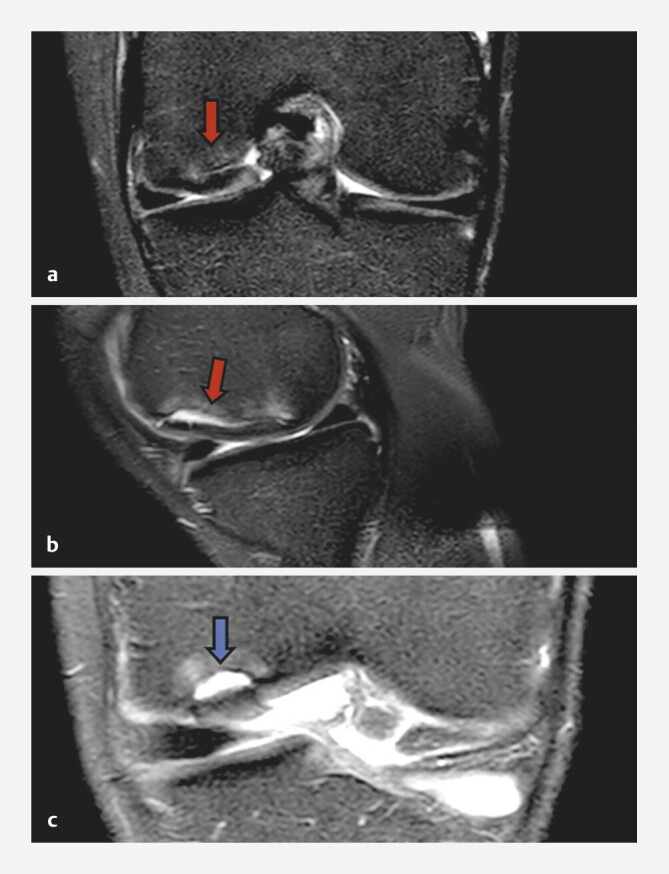

Methods: We describe a case of a patient suffering from OD with a bone lesion in the weight-bearing area of medial femoral condyle. Arthroscopy was performed and an osteochondral fragment from the medial femoral condyle was observed and two articular loose bodies were removed. After months, the patient returned with pain and a locked knee. magnetic resonance imaging (MRI) presented a new unstable chondral flap at the posterior border of the previous lesion. Surgery was performed again, and at open examination, the previous OD lesions were covered by regenerative tissue, with a lesion of 3 cm2 at the inferior medial part of the chondral flap. The peripheral margins were cleaned, and a subchondral crater was curetted. The subchondral lesion was debrided, and the flap was fixed with pins and a central bioresorbable screws.